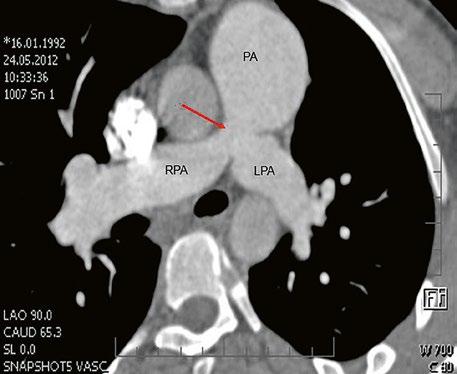

Supravalvární pulmonální stenóza a stenózy větví plicnice bývají součástí komplexních VSV (např. Fallotovy tetralogie) nebo syndromů (Williamsův syndrom, syndrom Noonanové, syndrom vrozené rubeoly, Alagillův syndrom aj.) (Obr. 45.39). Získané stenózy větví plicnice, ale i úplný uzávěr větve plicnice můžeme vidět po spojkových operacích podle BlalockaTaussigové (Obr. 45.40, Obr. 45.41). Pro zobrazení supravalvárních a periferních stenóz plicnice je optimální CT angiografie (Obr. 45.40, Obr. 45.41, Obr. 45.42, Obr. 45.43).

Obr. 45.42 CT angiografie. Dilatace kmene plicnice (PA), periferní stenóza v oblasti bifurkace a odstupu pravé větve plicnice (RPA) označena šipkou, odstup levé větve plicnice (LPA) je také lehce zúžen.